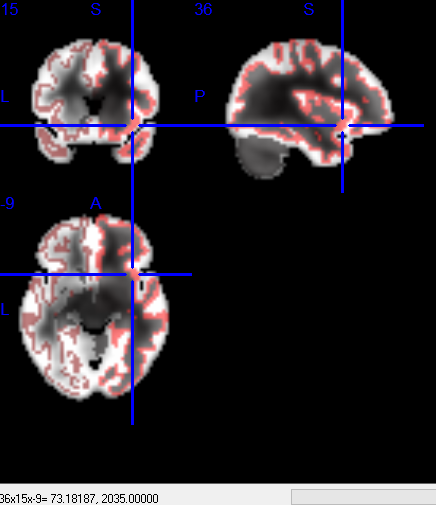

1)画图确认下ROI5.nii中的ROI是不是在你想要的地方,这一步很多软件都可以轻易完成。

临时使用一下上面得到的变换矩阵,做个图看看是不是经过变换的ROI是不是想要的位置。

同样可以做个图看看变换的结果lh.fsaverage.ROI5.mgh是不是在想要的位置。

变换后的DK模板map到mni152_T1

由于做了resample所以分辨率在mni152上看有所下降

变换后的DK模板map到某个结果上